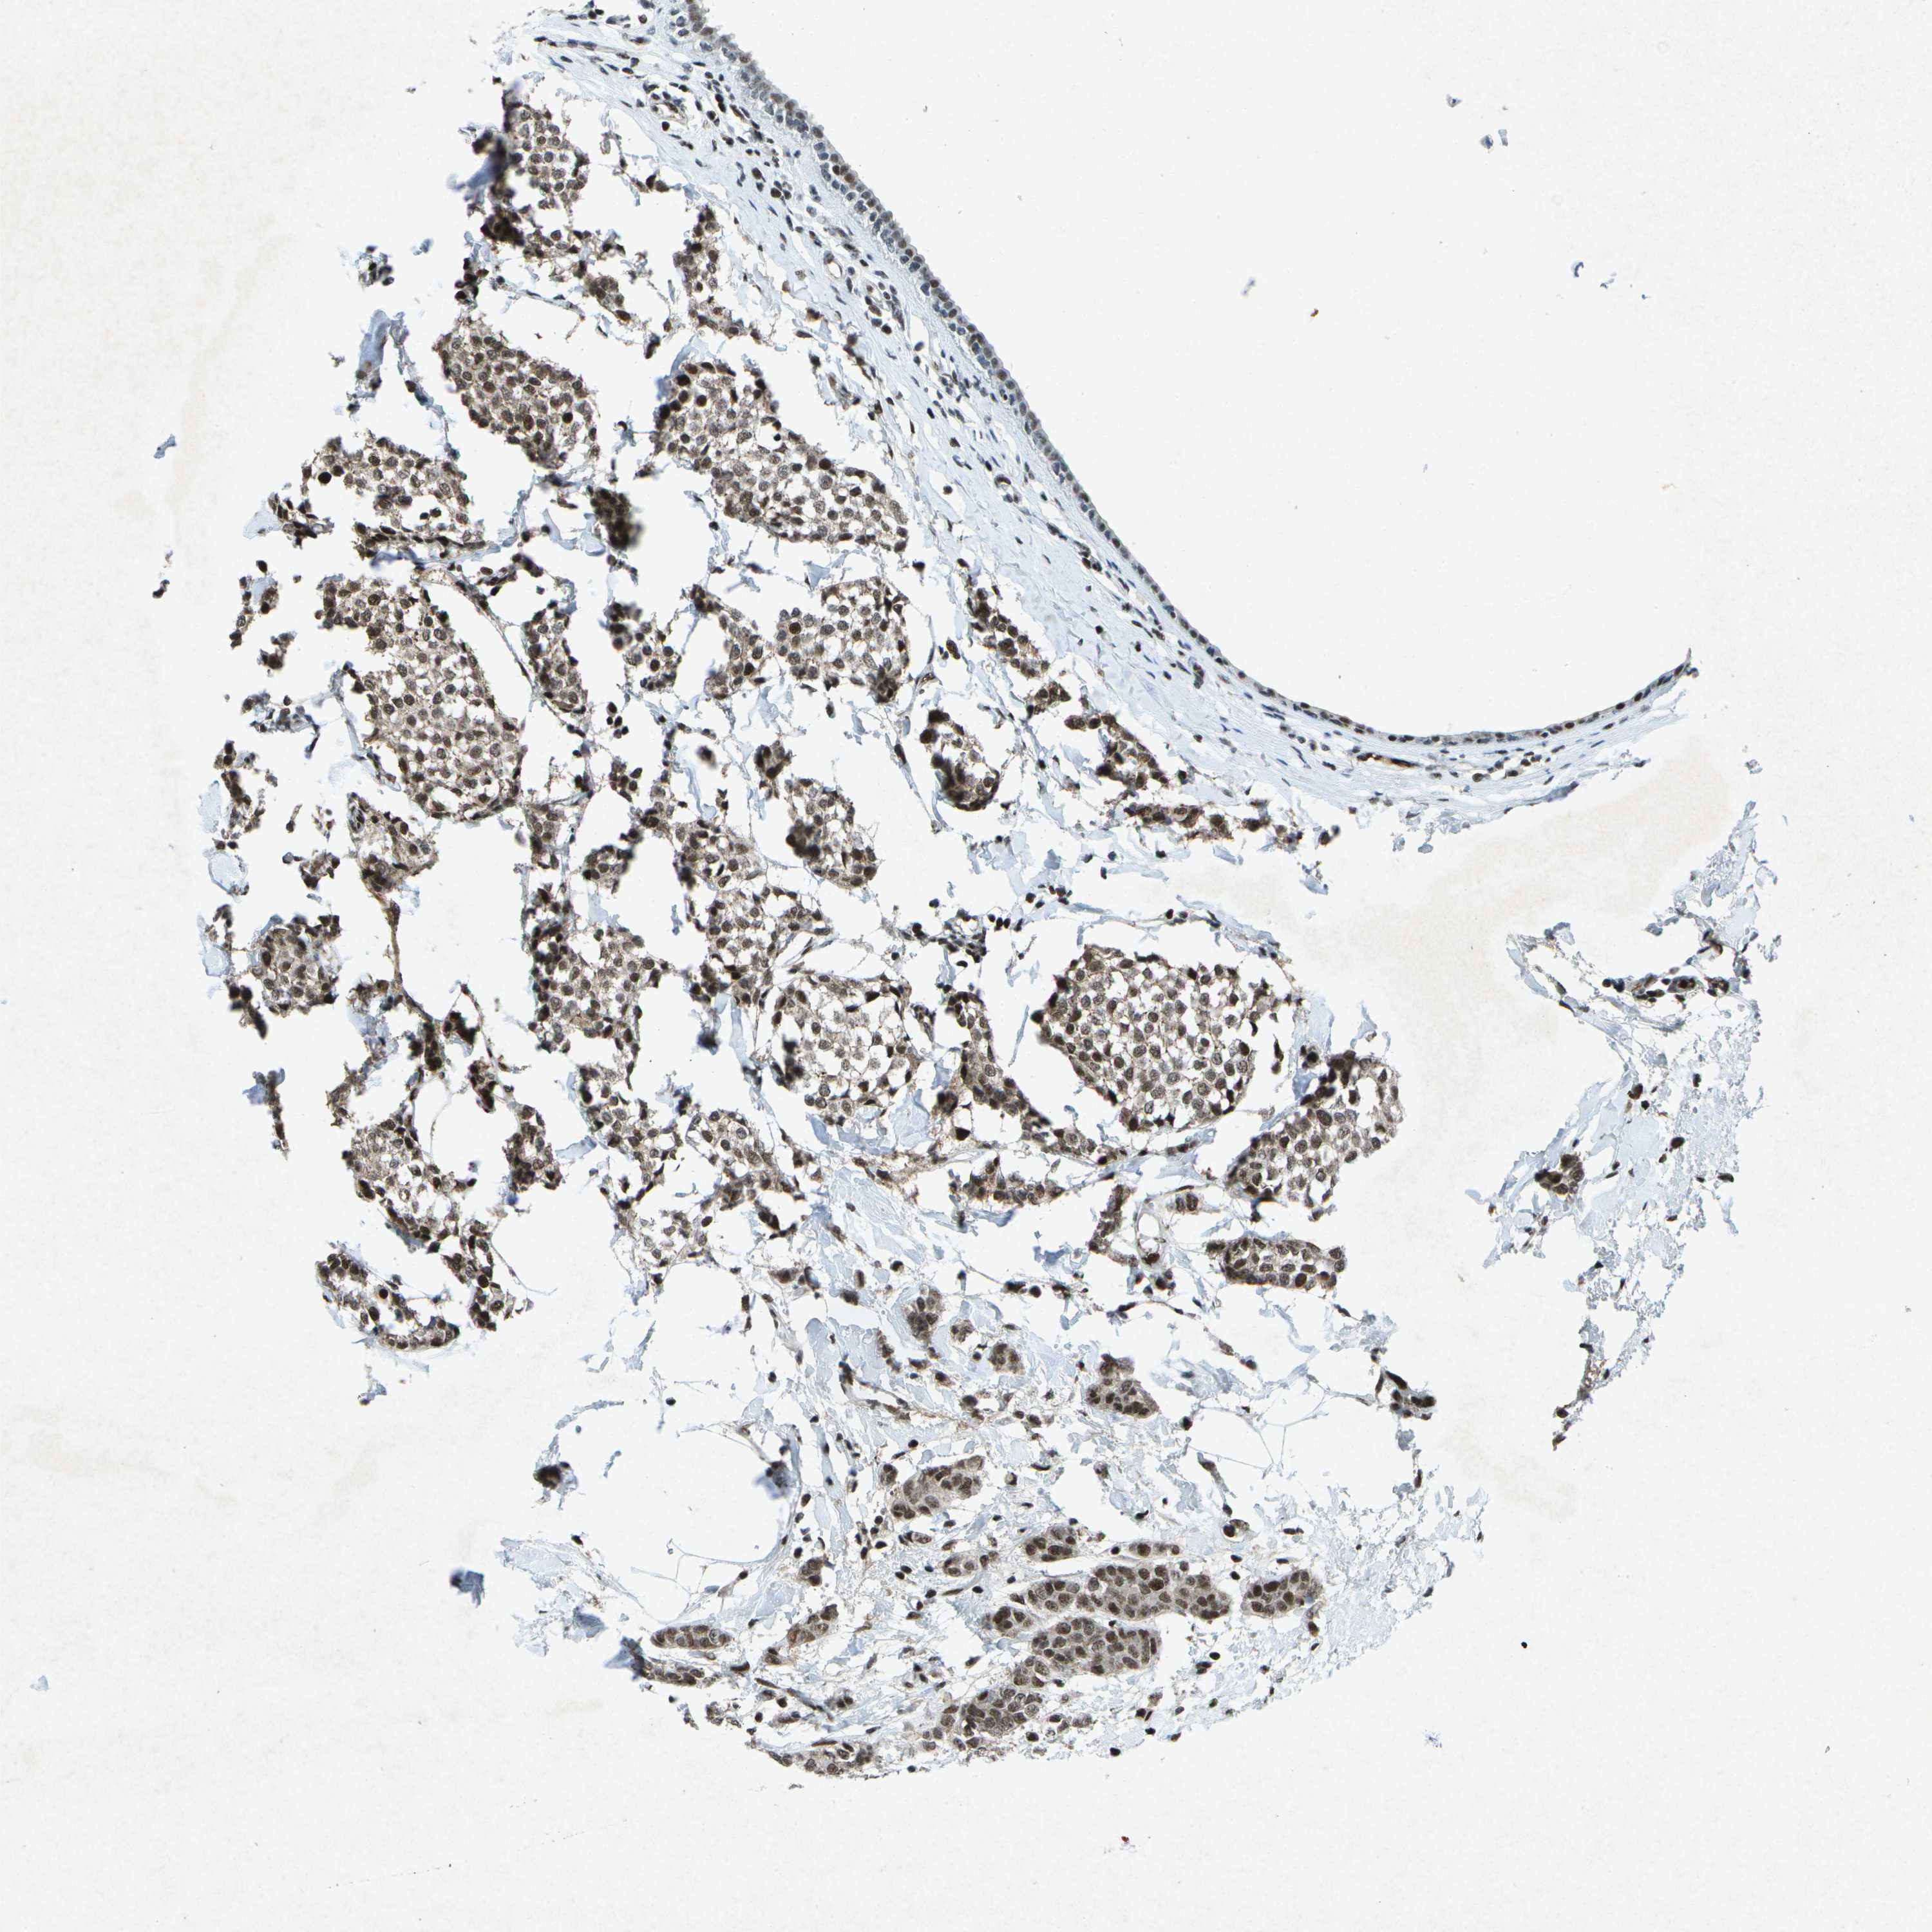

CANCER BREAST CANCER Show tissue menu

BRCA TCGA BRCA VALIDATION PROTEIN EXPRESSION

ANTIBODIES

AND

VALIDATION